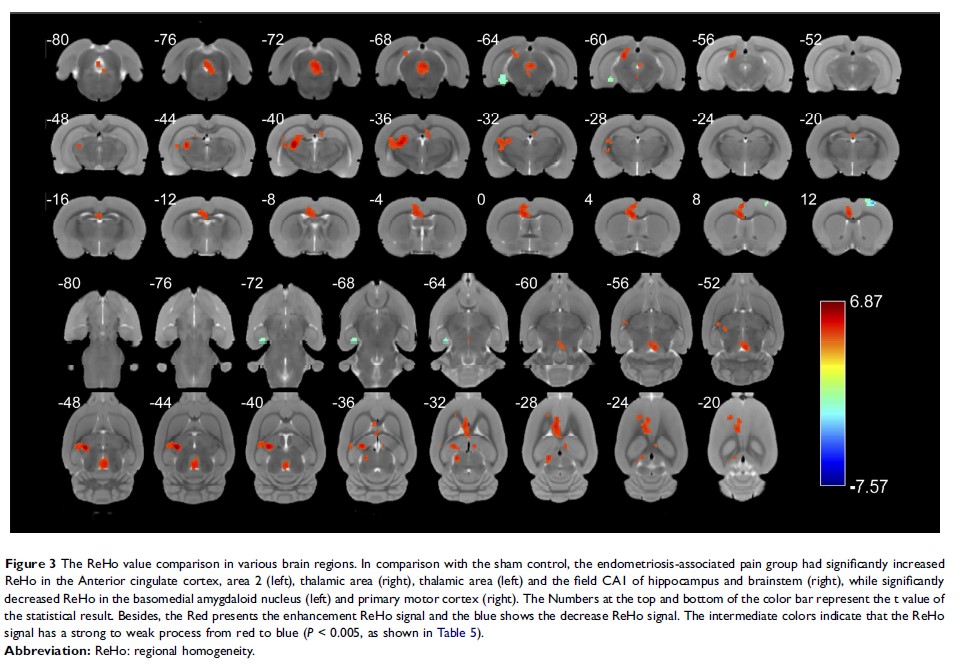

子宫内膜异位症相关疼痛大鼠模型脑功能活动相关的中枢敏感性变化